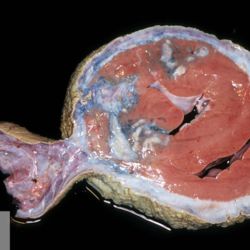

Pàgina anterior de 637 Pàgina següent 3181 total Wildlife Specie: Wildlife Organ: Heart Lesion: Pericarditis Lesion modifier: Pericarditis - Gangrenous Disease: - Files/Expedient: zoo17 Not viewed Wildlife Specie: Wildlife Organ: Heart Lesion: Pericarditis Lesion modifier: Pericarditis - Gangrenous Disease: - Files/Expedient: zoo17 Not viewed Wildlife Specie: Wildlife Organ: Heart Lesion: Pericarditis Lesion modifier: Pericarditis - Gangrenous Disease: - Files/Expedient: zoo17 Not viewed Non-human primate Specie: Non-human primate Organ: Liver Lesion: Cyst Lesion modifier: - Disease: - Not viewed Wildlife Specie: Wildlife Organ: Heart Lesion: Hemorrhage Lesion modifier: - Disease: - Not viewed Pàgina anterior de 637 Pàgina següent Títol Select...Avian (Exotic) (110)Avian (Poultry) (76)Bovine (317)Canine (935)Caprine (47)Equine (257)Feline (326)Ferret (19)General (127)Marine mammal (22)Non-human primate (20)Ovine (328)Porcine (379)Rabbit (61)Reptile (38)Rodent (28)Wildlife (91) Format Select...- (60)Abomasum (37)Adrenal gland (10)Blood (7)Blood vessel (50)Body as a whole (19)Bone (57)Bone marrow (21)Brain (93)Cloaca (1)Diaphragm (2)Ear (5)Esophagus (39)Eye (16)Fetus (12)Gallbladder (23)Gizzard (2)Heart (265)Intestine (356)Joint (32)Kidney (443)Larynx (5)Liver (326)Lung (264)Lymph node (91)Mammary gland (10)Mediastinum (1)Muscle (22)Nasal cavity (22)Nerve (7)Omasum (5)Oral cavity (63)Ovary (14)Oviduct (8)Pancreas (7)Parathyroid (5)Penis (10)Peritoneum (65)Pharynx (9)Pituitary gland (6)Placenta (7)Prostate (8)Proventriculus (3)Reticulum (1)Rumen (28)Sinus (7)Skin (181)Spinal cord (15)Spleen (105)Stomach (125)Teeth (1)Testicle (11)Thoracic cavity (31)Thymus (13)Thyroid gland (5)Tongue (32)Tonsils (11)Trachea (11)Urethra (5)Urinay bladder (61)Uterus (27)Vagina (1)Vulva (1)Yolk sac (1) Cobertura Select...- (152)Abomasitis (26)Abscess (27)Acidosis (1)Adenocarcinoma (20)Adenoma (9)Aerosacculitis (6)Agenesis (1)Agnathia (1)Alopecia (7)Amyloidosis (12)Aneurysm (6)Angiectasis (1)Anthracosis (1)Arteritis (11)Arthritis (15)Arthrogryposis (6)Artifact (4)Ascites (13)Atelectasis (8)Atherosclerosis (5)Atresia (1)Atrial septal defect (2)Atrophy (10)Autolysis (7)Bronchitis (6)Bronchopneumonia (26)Cachexia (2)Carcinoma (103)Cardiomyopathy (19)Cellulitis (2)Chemodectoma (4)Cholangiohepatitis (4)Cholangitis (19)Cholecystitis (4)Cholestasis (5)Chondrodysplasia (2)Chondrosarcoma (2)Chronic passive congestion (13)Chylothorax (2)Cirrhosis (6)Coelomitis (3)Coenurus cerebralis (4)Colitis (40)Congestion (17)Conjunctivitis (5)Coronitis (3)Cryptorchidism (3)Cyst (25)Cystitis (24)Dermatitis (69)Diaphragmatic hernia (4)Dilation (28)Discospondylitis (1)Disseminated intravascular coagulation (7)Dyschondroplasia (1)Dysplasia (29)Ectopia cordis (1)Ectopic ureter (1)Edema (55)Emphysema (5)Encephalitis (5)Endocardiosis (14)Endocarditis (26)Endometritis (5)Enteritis (118)Enterolith (6)Epulis (3)Esophagitis (14)Fasciitis (1)Fibrosis (7)Fibrous osteodystrophy (8)Fistula (1)Folliculitis (3)Fracture (2)Gastritis (34)Gingivitis (5)Glioma (8)Glomerulonephritis (21)Glossitis (25)Glycogenosis (1)Gout (8)Granuloma (2)Granulosa cell tumor (4)Hemangioma (9)Hemangiosarcoma (46)Hematoma (8)Hemoglobinuria (2)Hemopericardium (12)Hemoperitoneum (2)Hemorrhage (100)Hemosiderosis (7)Hemothorax (2)Hepatitis (78)Hernia (11)Histiocytosis (3)Hydatid cyst (11)Hydrocephalus (9)Hydrometra (1)Hydronephrosis (22)Hydropericardium (6)Hydrothorax (3)Hydroureter (5)Hyperkeratosis (8)Hyperostosis (4)Hyperplasia (37)Hypertrophy (9)Hypopigmentation (1)Hypoplasia (7)Hypopyon (1)Impaction (6)Infarction (63)Insulinoma (6)Intussusception (5)Jaundice (17)Laminitis (2)Laryngitis (2)Leiomyoma (5)Leukemia (13)Lipidosis (36)Lipoma (7)Lymphadenitis (45)Lymphadenopathy (7)Lymphangiectasia (6)Lymphangitis (5)Lymphoma (221)Malacia (11)Malignant melanoma (15)Mast cell tumor (11)Mastitis (8)Megaesophagus (2)Melanosis (3)Melena (4)Meningioma (6)Meningitis (6)Meningocele (2)Meningoencephalitis (5)Mesothelioma (5)Methemoglobinemia (2)Mineralization (10)Mucocele (5)Mucometra (1)Multilobular bone tumor (1)Mummification (3)Myelofibrosis (1)Myocarditis (4)Myositis (5)Necrosis (81)Nephritis (113)Nephroblastoma (6)Nephrosclerosis (1)Nephrosis (14)Neuritis (1)Obstruction (13)Omasitis (4)Omphalitis (1)Omphalophlebitis (7)Orchitis (4)Osteoarthrosis (5)Osteomyelitis (9)Otitis (2)Palatoschisis (3)Pancreatitis (3)Panniculitis (3)Papilloma (7)Parakeratosis (14)Patent ductus arteriosus (6)Peliosis hepatis (1)Perforation (17)Pericarditis (35)Peritonitis (39)Persistent right aortic arch (1)Pharyngitis (2)Pheochromocytoma (2)Phlebitis (2)Placentitis (6)Pleuritis (21)Pleuropneumonia (24)Pneumonia (109)Pneumothorax (3)Polycystosis (14)Polyp (5)Polyserositis (6)Posthitis (1)Proctitis (4)Prolapse (3)Prostatitis (3)Proventriculitis (1)Pyelonephritis (24)Pyometra (6)Pyothorax (4)Rhinitis (11)Rumenitis (6)Rupture (24)Salpingitis (3)Sarcoma (57)Sclerosis (1)Scoliosis (2)Seminoma (2)Sequestrum (2)Serous atrophy (14)Sinusitis (7)Splenitis (14)Splenomegaly (9)Spondylitis (6)Spondylosis (1)Stenosis (9)Stomatitis (32)Tenosynovitis (2)Teratoma (3)Thricobezoar (2)Thrombosis (16)Tonsilitis (4)Torsion (13)Tracheitis (4)Tympany (7)Typhlitis (8)Typhlocolitis (4)Ulcer (43)Urethritis (1)Urolithiasis (36)Uroperitoneum (1)Uveitis (1)Vasculitis (15)Ventricular septal defect (3)Volvulus (11) Matèria Select... - (14)- (1653)- (152)Abomasitis - Catarrhal (2)Abomasitis - Catarrhal-hemorrhagic (1)Abomasitis - Chronic (1)Abomasitis - Fibrinous-necrotizing (2)Abomasitis - Hyperplasic (5)Abomasitis - Hyperplasic - Chronic (1)Abomasitis - Necrotic (1)Abomasitis - Necrotizing (2)Abomasitis - Ulcerative (5)Adenocarcinoma (9)Aerosacculitis - Granulomatous (1)Amyloidosis - Chronic (1)Arteritis - Necrotic (2)Arteritis - Necrotizing (1)Arthritis - Chronic (4)Arthritis - Fibrinous-purulent (3)Arthritis - Serous (4)Arthritis - Subacute (1)Ascites - Serous (1)Atrophy - Serous (1)Bronchitis - Catarrhal (3)Bronchitis - Suppurative (1)Bronchopneumonia - Catarrhal-purulent (17)Bronchopneumonia - Fibrinous (1)Bronchopneumonia - Granulomatous (1)Bronchopneumonia - Purulent (1)Bronchopneumonia - Suppurative (5)Carcinoma - Adenocarcinoma (33)Carcinoma - Adenocarcinoma - Hepatocellular (2)Carcinoma - Adenocarcinoma - Mucinous (1)Carcinoma - Basosquamous (1)Carcinoma - Cholangiocellular (3)Carcinoma - Hepatocellular (4)Carcinoma - Metastatic (3)Carcinoma - Squamous cell carcinoma (13)Carcinoma - Transitional cell (2)Cardiomyopathy - Dilated (13)Cardiomyopathy - Hypertrophic (6)Cellulitis - Necrotizing (1)Cholangitis - Chronic (8)Cholangitis - Hyperplasic (3)Cholecystitis - Fibrinous-necrotizing (1)Coelomitis - Fibrinous (1)Coelomitis - Granulomatous (1)Colitis - Catarrhal (3)Colitis - Catarrhal-hemorrhagic (1)Colitis - Fibrinous (1)Colitis - Fibrinous-necrotizing (1)Colitis - Fibrinous-necrotizing (Diphtheritic) (6)Colitis - Granulomatous (2)Colitis - Hemorrhagic (4)Colitis - Hemorrhagic-necrotizing (3)Colitis - Necrotizing (2)Colitis - Ulcerative (6)Congestion - Chronic (2)Conjunctivitis - Hyperplasic (1)Conjunctivitis - Purulent (3)Coronitis - Ulcerative (1)Cystitis - Chronic (3)Cystitis - Fibrinous (1)Cystitis - Fibrinous-necrotizing (1)Cystitis - Follicular (1)Cystitis - Hemorrhagic (6)Cystitis - Hemorrhagic-ulcerative (1)Cystitis - Necrotizing (9)Cystitis - Perforated (1)Dermatitis - Granulomatous (14)Dermatitis - Hyperkeratotic (10)Dermatitis - Hyperplasic (proliferative) (1)Dermatitis - Hyperplastic (10)Dermatitis - Necrotizing (4)Dermatitis - Pustular (4)Dermatitis - Ulcerative (2)Dilation - Chronic (1)Discospondylitis - Necrotizing (1)Dysplasia - Follicular (5)Edema - Interstitial (6)Emphysema - Interstitial (1)Encephalitis - Granulomatous (1)Encephalitis - Nonsuppurative (1)Endocardiosis - Mitral (7)Endocardiosis - Mitral - Chronic (5)Endocarditis - Valvular (6)Endocarditis - Valvular - Mitral (7)Endocarditis - Valvular - Pulmonic (1)Endocarditis - Valvular - Subacute (1)Endocarditis - Valvular - Subaortic (5)Endocarditis - Valvular - Tricuspid (4)Endometritis - Purulent (3)Endometritis - Purulent-hemorrhagic (2)Enteritis - Catarrhal (23)Enteritis - Catarrhal - Acute (1)Enteritis - Catarrhal-hemorrhagic (5)Enteritis - Catarrhal-hemorrhagic - Acute (2)Enteritis - Fibrinous (16)Enteritis - Fibrinous - Acute (3)Enteritis - Fibrinous-necrotizing (7)Enteritis - Granulomatous (14)Enteritis - Granulomatous - Chronic (1)Enteritis - Granulomatous - Multifocal (1)Enteritis - Hemorrhagic (17)Enteritis - Hemorrhagic - Acute (1)Enteritis - Hemorrhagic-necrotizing (1)Enteritis - Hyperplasic (proliferative) (4)Enteritis - Necrotizing (4)Enteritis - Necrotizing - Acute (1)Enteritis - Necrotizing - Hemorrhagic (1)Enteritis - Necrotizing-ulcerative (2)Enteritis - Ulcerative (1)Enteritis - Ulcerative-hemorrhagic (1)Esophagitis - Erosive-ulcerative (6)Esophagitis - Necrotizing (4)Esophagitis - Ulcerative (1)Esophagitis - Ulcerative-necrotizing (1)Fasciitis - Fibrinous-purulent (1)Folliculitis - Purulent (2)Gastritis - Catarrhal (2)Gastritis - Chronic (1)Gastritis - Follicular (1)Gastritis - Hemorrhagic (2)Gastritis - Hemorrhagic-necrotizing (1)Gastritis - Hypertrophic (2)Gastritis - Inclusion bodies (1)Gastritis - Mineralization (1)Gastritis - Mycotic (1)Gastritis - Necrotizing (2)Gastritis - Ulcerative (6)Gastritis - Uremic (3)Gingivitis - Erosive (2)Gingivitis - Hyperplasic (proliferative) (1)Gingivitis - Necrotizing (1)Glomerulonephritis - Chronic (7)Glomerulonephritis - Membranoproliferative (3)Glomerulonephritis - Membranoproliferative - Chronic (1)Glomerulonephritis - Membranous (3)Glomerulonephritis - Membranous - Chronic (1)Glomerulonephritis - Proliferative (2)Glomerulonephritis - Subacute (1)Glossitis - Erosive (2)Glossitis - Granulomatous (6)Glossitis - Hyperplasic (1)Glossitis - Hyperplasic (proliferative) (2)Glossitis - Hyperplastic (1)Glossitis - Necrotizing (2)Glossitis - Necrotizing - Focal (1)Glossitis - Ulcerative (6)Glossitis - Ulcerative - Multifocal (1)Glossitis - Ulcerative - Subacute (1)Glycogenosis (1)Granuloma - Eosinophilic (1)Hemangiosarcoma - Metastatic (2)Hemorrhage - Acute (1)Hemorrhage - Subcapsular (3)Hepatitis - Abscess (9)Hepatitis - Acute (3)Hepatitis - Chronic (4)Hepatitis - Chronic interstitial (6)Hepatitis - Granulomatous (7)Hepatitis - Interstitial - Multifocal (1)Hepatitis - Interstitial - Subacute (1)Hepatitis - Necrotizing (17)Hepatitis - Necrotizing - Acute (2)Hepatitis - Necrotizing - Hemorrhagic (1)Hepatitis - Necrotizing - Subacute (1)Hepatitis - Pyogranulomatous (7)Hepatitis - Subacute (4)Hydronephrosis - Chronic (1)Hydropericardium - Chronic (1)Hyperplasia - Erythroid (1)Hyperplasia - Lymphoid (3)Hyperplasia - Myeloid (1)Hyperplasia - Nodular (8)Hypertrophy - Concentric (2)Hypertrophy - Eccentric (3)Infarction - Acute (17)Infarction - Acute - Multifocal (2)Infarction - Chronic (5)Infarction - Chronic - Multifocal (1)Infarction - Subacute (18)Infarction - Subacute - Focal (2)Laminitis - Chronic (2)Laryngitis - Necrotic (1)Laryngitis - Necrotizing (1)Leukemia - Lymphoid leukemia (2)Leukemia - Non-lymphoid leukemia (6)Lipidosis - Multifocal (1)Lipidosis - Panlobular (1)Lipidosis - Panlobular - Generalized (2)Lymphadenitis - Granulomatous (24)Lymphadenitis - Granulomatous - Chronic (3)Lymphadenitis - Hemorrhagic (1)Lymphadenitis - Necrotizing (5)Lymphadenitis - Necrotizing (caseous) (11)Lymphangitis - Granulomatous (1)Lymphangitis - Purulent (1)Lymphangitis - Ulcerative (1)Lymphoma - Alimentary lymphoma (7)Lymphoma - Cutaneous lymphoma (6)Lymphoma - Lymphosarcoma (2)Lymphoma - Mediastinal lymphoma (1)Lymphoma - Multicentric lymphoma (29)Malignant melanoma - Malignant (1)Malignant melanoma - Metastatic (1)Mast cell tumor - Metastatic (1)Mastitis - Fibrinous-purulent (2)Mastitis - Necrotic (1)Mastitis - Purulent (3)Mastitis - Suppurative (1)Meningitis - Fibrinous-purulent (2)Meningitis - Purulent (4)Meningoencephalitis - Necrotizing (3)Meningoencephalitis - Nonsuppurative (2)Mineralization - Metastatic (4)Myocarditis - Fibrous - Chronic (1)Myocarditis - Granulomatous (1)Myositis - Purulent (2)Necrosis - Acute (1)Necrosis - Cortical (5)Necrosis - Follicular (1)Necrosis - Papillary (8)Necrosis - Papillary - Acute (3)Necrosis - Subacute (3)Necrosis - Tubular (6)Nephritis - Embolic (2)Nephritis - Embolic suppurative (7)Nephritis - Granulomatous (27)Nephritis - Granulomatous - Chronic (1)Nephritis - Granulomatous - Multifocal (1)Nephritis - Interstitial (6)Nephritis - Interstitial - Acute (4)Nephritis - Interstitial - Chronic (41)Nephritis - Interstitial - Subacute (12)Nephritis - Purulent (7)Nephritis - Purulent - Acute (2)Nephritis - Purulent - Multifocal (3)Nephrosis - Cholemic (3)Nephrosis - Hemoglobinuric (10)Omasitis - Fibrinous-necrotizing (1)Omasitis - Hyperkeratotic (1)Omasitis - Necrotizing (2)Omphalophlebitis - Fibrinous-purulent (2)Omphalophlebitis - Purulent (3)Orchitis - Necrotizing (1)Osteomyelitis - Necrotizing (7)Osteomyelitis - Purulent (2)Otitis - Necrotizing (1)Otitis - Proliferative (1)Pancreatitis - Acute (1)Pancreatitis - Chronic (1)Pancreatitis - Granulomatous (1)Panniculitis - Fibrinous-purulent (1)Panniculitis - Necrotic (1)Panniculitis - Parasitic (1)Perforation - Acute (2)Pericarditis - Fibrinous (19)Pericarditis - Fibrinous - Subacute (1)Pericarditis - Fibrinous-necrotizing (1)Pericarditis - Fibrinous-purulent (3)Pericarditis - Fibrous (1)Pericarditis - Fibrous - Chronic (1)Pericarditis - Gangrenous (6)Pericarditis - Granulomatous (1)Pericarditis - Granulomatous - Chronic (2)Peritonitis - Acute (1)Peritonitis - Fibrinous (11)Peritonitis - Fibrinous - Subacute (1)Peritonitis - Fibrinous-purulent (5)Peritonitis - Fibrous (3)Peritonitis - Granulomatous (6)Peritonitis - Purulent (1)Peritonitis - Purulent-hemorrhagic (1)Peritonitis - Pyogranulomatous (3)Pharyngitis - Fibrinous-necrotizing (1)Pharyngitis - Ulcerative (1)Pheochromocytoma - Metastatic (1)Phlebitis - Purulent (1)Placentitis - Fibrinous-necrotizing (1)Placentitis - Necrotic (1)Placentitis - Necrotizing (1)Pleuritis - Chronic (1)Pleuritis - Fibrinous (3)Pleuritis - Fibrinous-purulent (2)Pleuritis - Fibrous (2)Pleuritis - Granulomatous (3)Pleuritis - Hyperplastic (2)Pleuritis - Purulent (2)Pleuritis - Pyogranulomatous (1)Pleuropneumonia - Fibrinous (13)Pleuropneumonia - Fibrinous-necrotizing (5)Pleuropneumonia - Granulomatous (2)Pleuropneumonia - Hemorrhagic-necrotizing (4)Pneumonia - Aspiration (11)Pneumonia - Bronchointerstitial (4)Pneumonia - Bronchointerstitial - Subacute (1)Pneumonia - Embolic (5)Pneumonia - Granulomatous (37)Pneumonia - Granulomatous - Multifocal (4)Pneumonia - Hemorrhagic-necrotizing (2)Pneumonia - Interstitial (7)Pneumonia - Interstitial - Acute (8)Pneumonia - Interstitial - Chronic (6)Pneumonia - Interstitial - Subacute (15)Pneumonia - Necrotizing (2)Pneumonia - Pyogranulomatous (2)Pneumonia - Verminous (5)Polyserositis - Fibrinous (6)Polyserositis - Fibrous (1)Proctitis - Fibrinous-necrotizing (1)Proctitis - Parasitic (2)Prostatitis - Purulent (1)Pyelonephritis - Acute (2)Pyelonephritis - Chronic (3)Rhinitis - Catarrhal (2)Rhinitis - Fibrinous (1)Rhinitis - Granulomatous (4)Rhinitis - Purulent (3)Rumenitis - Acute (1)Rumenitis - Erosive (1)Rumenitis - Necrotizing (1)Rupture - Acute (3)Sarcoma - Fibrosarcoma (12)Sarcoma - Hemangiosarcoma (11)Sarcoma - Histiocytic (7)Sarcoma - Metastatic (1)Sarcoma - Multilobular tumor of bone (1)Sequestrum - Chronic (2)Sinusitis - Suppurative (1)Splenitis - Granulomatous (8)Splenitis - Granulomatous - Chronic (1)Splenitis - Necrotizing (3)Splenitis - Necrotizing (caseous) (2)Spondylitis - Necrotizing (2)Stenosis - Intestinal (1)Stenosis - Valvular - Subaortic (4)Stomatitis - Erosive (12)Stomatitis - Erosive-ulcerative (3)Stomatitis - Fibrinous-necrotizing (1)Stomatitis - Fibrinous-necrotizing (Diphtheritic) (1)Stomatitis - Granulomatous (1)Stomatitis - Hyperplasic (1)Stomatitis - Hyperplasic (proliferative) (1)Stomatitis - Necrotizing (2)Stomatitis - Ulcerative (5)Stomatitis - Ulcerative - Multifocal (1)Stomatitis - Ulcerative-necrotizing (1)Tonsilitis - Necrotizing (4)Torsion - Acute passive hyperemia (5)Tracheitis - Catarrhal (3)Tracheitis - Fibrinous (1)Tracheitis - Granulomatous (1)Typhlitis - Catarrhal (1)Typhlitis - Fibrinous-necrotizing (2)Typhlitis - Hemorrhagic (2)Typhlitis - Ulcerative-hemorrhagic (1)Typhlocolitis - Fibrinous-necrotizing (2)Typhlocolitis - Proliferative (1)Ulcer - Chronic (6)Ulcer - Multifocal (2)Ulcer - Mycotic (1)Ulcer - Perforated (6)Urethritis - Hemorrhagic (1)Urolithiasis - Chronic (2)Uveitis - Granulomatous (1)Vasculitis - Granulomatous (1)Vasculitis - Necrotizing (1) Editor Select...- (1970)Acidosis (2)Actinobacillosis (Pleuropneumonia) (11)Aelurostrongylosis (2)African horse sickness (13)African swine fever (14)Alopecia X (1)Anaplasmosis (4)Anthrax (2)Aortic thromboembolism (feline) (7)Ascariasis (15)Aspergillosis (18)Atopic dermatitis (1)Atrophic rhinitis (3)Babesiosis (6)Blackhead (1)Bluetongue (11)Border disease (2)Bovine viral diarrhea (21)Brucellosis (2)Candidiasis (5)Canine distemper (14)Caprine arthritis-encephalitis (2)Capture myopathy (1)Cardiac insufficiency (17)Caseous lymphadenitis (7)Chlamydiosis (2)Classical swine fever (19)Clostridiosis (19)Coccidiosis (9)Coenurosis (4)Colibacillosis (21)Contagious ecthyma (7)Copper toxicosis (11)Cowdriosis (Heartwater) (3)Cryptococcosis (3)Cryptosporidiosis (2)Cysticercosis (23)Demodicosis (1)Diabetes (1)Dicrocoeliosis (5)Dictyocaulosis (4)Dirofilariasis (7)Discoid lupus erythematosus (3)Echinococcosis (17)Edema disease (7)Egg drop syndrome (1)Encephalitozoonosis (5)Enterotoxemia (1)Enzootic bovine leukosis (46)Epitheliogenesis imperfecta (3)Equine rhinopneumonitis (2)Equine verminous arteritis (strongylosis) (7)Erysipelas (5)Exudative epidermitis (7)Fasciolasis (11)Feline eosinophilic dermatoses (1)Feline hepatic lipidosis (8)Feline histiocytosis (4)Feline infectious peritonitis (38)Feline leukemia (4)Feline lower urinary tract disease (3)Feline panleukopenia (16)Feline viral rhinotracheitis (1)Flea allergy dermatitis (1)Foot and mouth disease (2)Gasterophilosis (4)Glasser's disease (15)Gousiekte (4)Gout (6)Haemonchosis (9)Hemolytic anemia (4)Hemorrhagic diathesis (1)Hepatic insufficiency (11)Hepatosis dietetica (7)Herpesvirosis (6)Hyperadrenocorticism (7)Hyperparathyroidism (10)Hypertrophic osteopathy (6)Hypervitaminosis D (1)Hypodermosis (1)Inclusion body hepatitis (4)Infectious bovine rhinotracheitis (5)Infectious bronchitis (5)Infectious canine hepatitis (13)Influenza (4)Juvenile nephropathy (8)Lamb dysentery (4)Leishmaniasis (28)Leptospirosis (1)Leukosis (5)Listeriosis (4)Lumpy skin disease (3)Maedi-visna (4)Malignant catarrhal fever (12)Mange (6)Mannheimiosis (5)Marek's disease (7)Metabolic bone disease (2)Mucoid enteropathy (5)Mulberry heart disease (5)Myasis (1)Mycobacteriosis (22)Mycosis fungoides (6)Myxomatosis (3)Necrobacillosis (5)Neonatal isoerythrolysis (6)Nocardiosis (4)Oestrosis (2)Onchocerciasis (1)Osteochondrosis (1)Ostertagiosis (6)Ovine pulmonary adenocarcinoma (5)Oxyuriasis (1)Pacheco's disease (4)Papillomatosis (6)Paratuberculosis (18)Parvovirosis (17)Pasteurellosis (11)Pemphigus foliaceus (1)Periodontal disease (1)Polioencephalomalacia of ruminants (4)Polyarteritis nodosa (3)Polycystic kidney disease (13)Porcine circovirosis (11)Porcine dermatitis and nephropathy syndrome (9)Porcine proliferative enteropathy (4)Porcine reproductive and respiratory syndrome (6)Porcine stress syndrome (1)Pox (13)Pregnancy toxemia (3)Proventricular dilatation disease (2)Pseudotuberculosis (yersiniosis) (2)Psittacine beak and feather disease (PBFD) (5)Pyoderma (4)Q fever (4)Rabbit hemorrhagic disease (2)Renal insufficiency (12)Reticuloendotheliosis (2)Rhodococcosis (1)Rickets (1)Rinderpest (2)Salmonellosis (34)Sarcosporidiosis (2)Schmallenberg (7)Septicemia (23)Spirocercosis (11)Streptococcosis (5)Strongylosis (1)Swine dysentery (5)Systemic coronavirosis (5)Tetralogy of Fallot (5)Theileriosis (13)Thromboembolism (5)Toxoplasmosis (11)Transmissible viral proventriculitis (1)Traumatic reticuloperitonitis (3)Traumatism (16)Tuberculosis (58)Ulcerative lymphangitis (1)Uremic syndrome (20)Viral arthritis (6)White muscle disease (9)Wobbler syndrome (2)Xanthomatosis (1)Zygomycosis (4) Idioma Select...- (1180)Bacterial (501)Degeneration (106)Fungal (46)Hemodynamic (112)Idiopathic (22)Inflammation (58)Malformation (88)Neoplasia (343)Nutritional (41)Parasitic (243)Physical/Chemical (93)Toxic (44)Viral (304) Ítem destacat Canine Puppy. Corneal edema